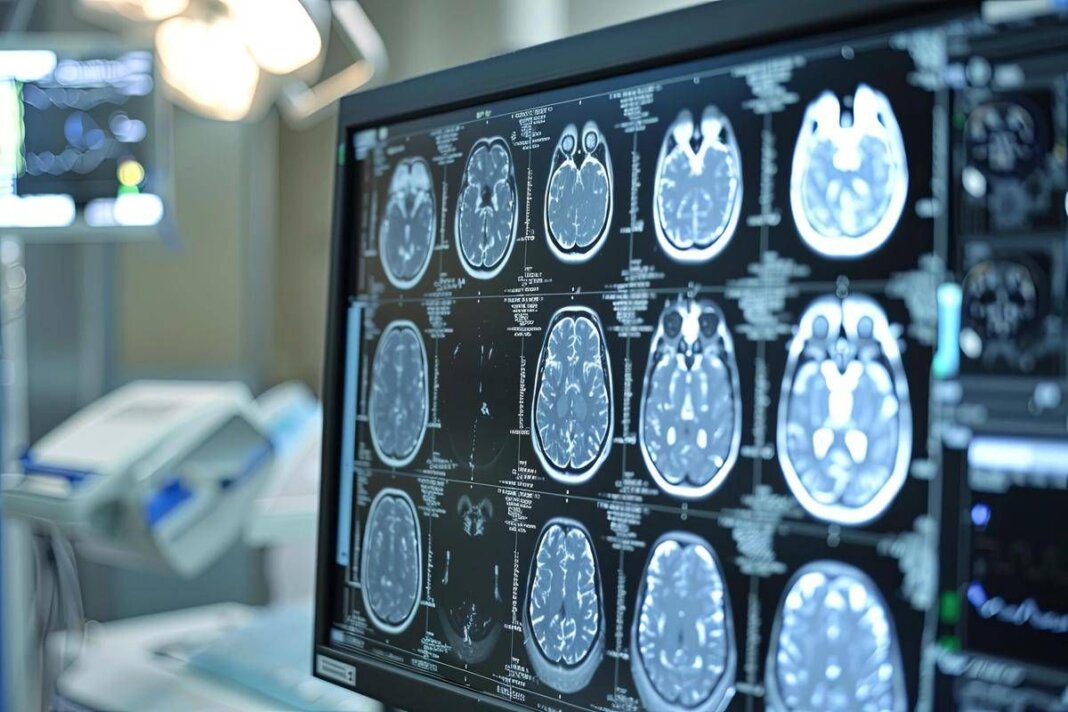

Neoplasie cerebrali, in Italia ogni anno 3mila casi di glioma

(Adnkronos) – Una volta erano considerate delle neoplasie rare, ma oggi i gliomi sono sempre più diffusi. In Italia i casi annui ammontano a oltre 3mila e corrispondono al 40% di tutti i tumori cerebrali primitivi. Tra i gliomi, quelli di basso grado di frequenza più rara rappresentano una sfida clinica rilevante anche per la loro evoluzione e l’assenza di trattamenti mirati, oltre alla resistenza che dimostrano ai trattamenti convenzionali. Sono malattie orfane di cui si parla poco anche fra i clinici, tra le istituzioni e sui media. Perciò la Fondazione Aiom (Associazione italiana di oncologia medica) ha lanciato nei mesi scorsi ‘I gliomi’, una campagna nazionale online di formazione e informazione. Sono stati organizzati webinar rivolti agli oncologi medici e alle altre figure sanitarie coinvolte nel team multidisciplinare. Sono stati indirizzati a pazienti e caregiver ulteriori eventi online insieme a un’attività di sensibilizzazione sui principali social media. I risultati dell’iniziativa sono presentati oggi in una conferenza stampa virtuale promossa da Fondazione Aiom. Il progetto è stato realizzato con il contributo non condizionante del Gruppo Servier in Italia.

“Sono tumori cerebrali molto complessi e che spesso vengono diagnosticati in età giovanile – afferma Saverio Cinieri, presidente di Fondazione Aiom – Si sviluppano da cellule del cervello chiamate gliali e possono avere una prognosi variabile, ma potenzialmente a lungo termine. La gestione della patologia richiede una stretta collaborazione fra neurochirurgo, radioterapista e oncologo medico. Attraverso il bisturi è possibile rescindere la massa tumorale oppure eseguire una biopsia grazie a nuove e sofisticate tecnologie. La radioterapia permette di ridurre il rischio di recidiva o eliminare quella parte di cancro che non è stato possibile rimuovere chirurgicamente. Viene somministrata insieme alla chemioterapia e le sedute sono di solito diluite nel corso del tempo, per limitare l’impatto degli effetti collaterali. Infine, l’oncologo medico deve scegliere i farmaci da somministrare e deve selezionarli valutando le condizioni cliniche del singolo paziente”.

“Anche per il trattamento dei gliomi, in particolare quelli di basso grado, si può ricorrere all’oncologia di precisione che potrà ridisegnare la pratica clinica nel prossimo futuro – illustra Enrico Franceschi, direttore dell’Oncologia del sistema nervoso all’Irccs Istituto delle scienze neurologiche di Bologna – E’ molto importante verificare la presenza o meno delle mutazioni Idh1 e Idh2. Questi biomarcatori indicano specifiche patologie caratterizzate da una prognosi decisamente più favorevole e maggiore sensibilità dei gliomi alla radio e chemioterapia. Al momento della diagnosi è quindi essenziale l’esecuzione precoce di alcuni test molecolari per identificare al meglio i diversi sottotipi di gliomi. Tra le terapie di nuova generazione vi è anche vorasidenib, un farmaco orale inibitore Idh1 e Idh2 che ha dimostrato di essere un trattamento efficace nel posticipare la radio e chemioterapia nei gliomi di basso grado ed è una rilevante innovazione medico-scientifica”.